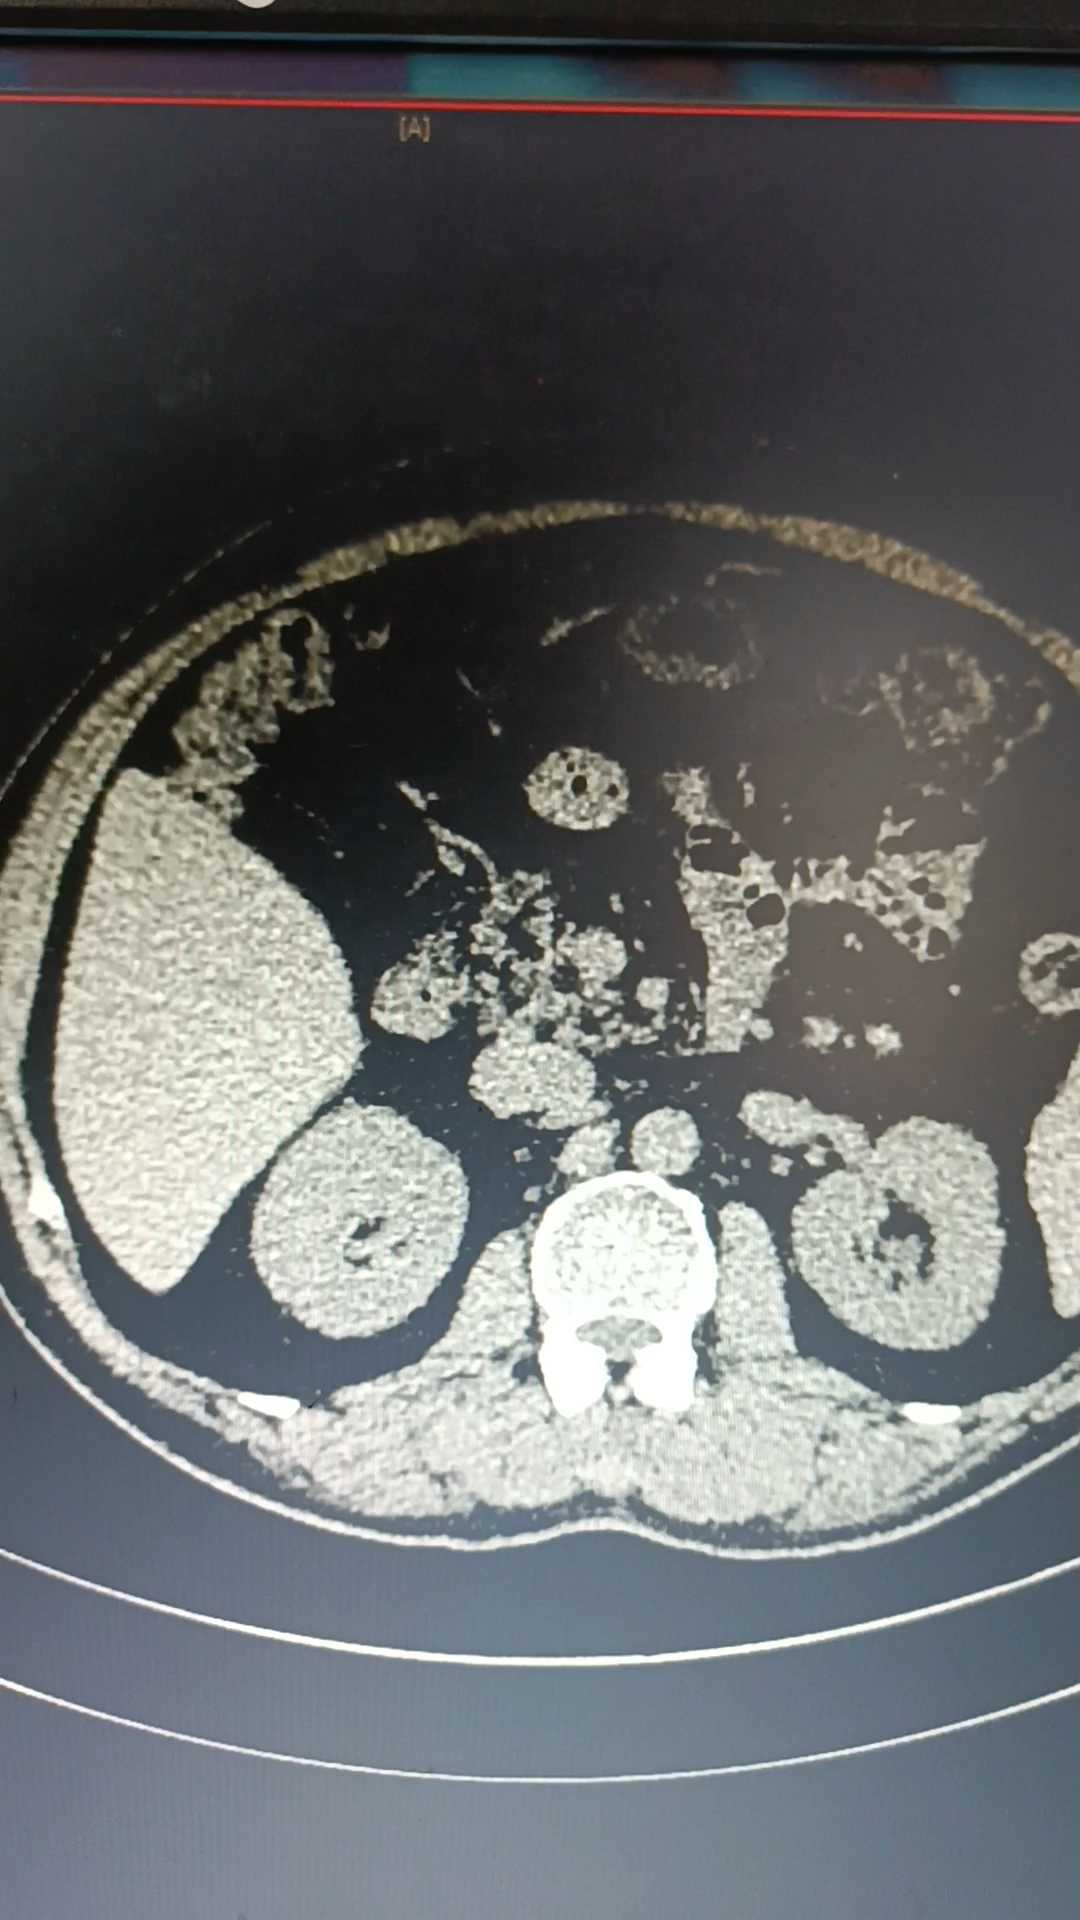

从彩超上看到了什么?

①右下腹肿块,肠系膜囊肿?

②双侧腹股沟疝。

这就有讨教了,这个肿物肯定要进一步明确诊断,腹股沟疝暂时搁置。

从目前来看,阑尾囊腺瘤可能性很大。

这例呢,从影像彩超辅助检查中看瘤体不小,开刀无疑也是种不错的办法。但腔镜也更能探查腹腔其他地方有无病变。